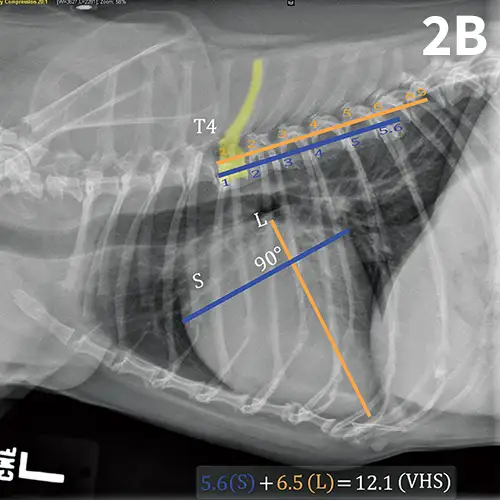

Progressive cardiomegaly noted on annual evaluations in a dog with MVD.

The VHS has been shown to be useful when determining whether a cough is cardiogenic, pulmonary, or mixed in origin for dogs with MVD.9 One study found that a VHS >12.0 was suggestive for a cardiac component to cough in dogs with MVD.9 It is important to note that among these dogs, some were determined to have a cough of mixed cardiac and pulmonary origin.